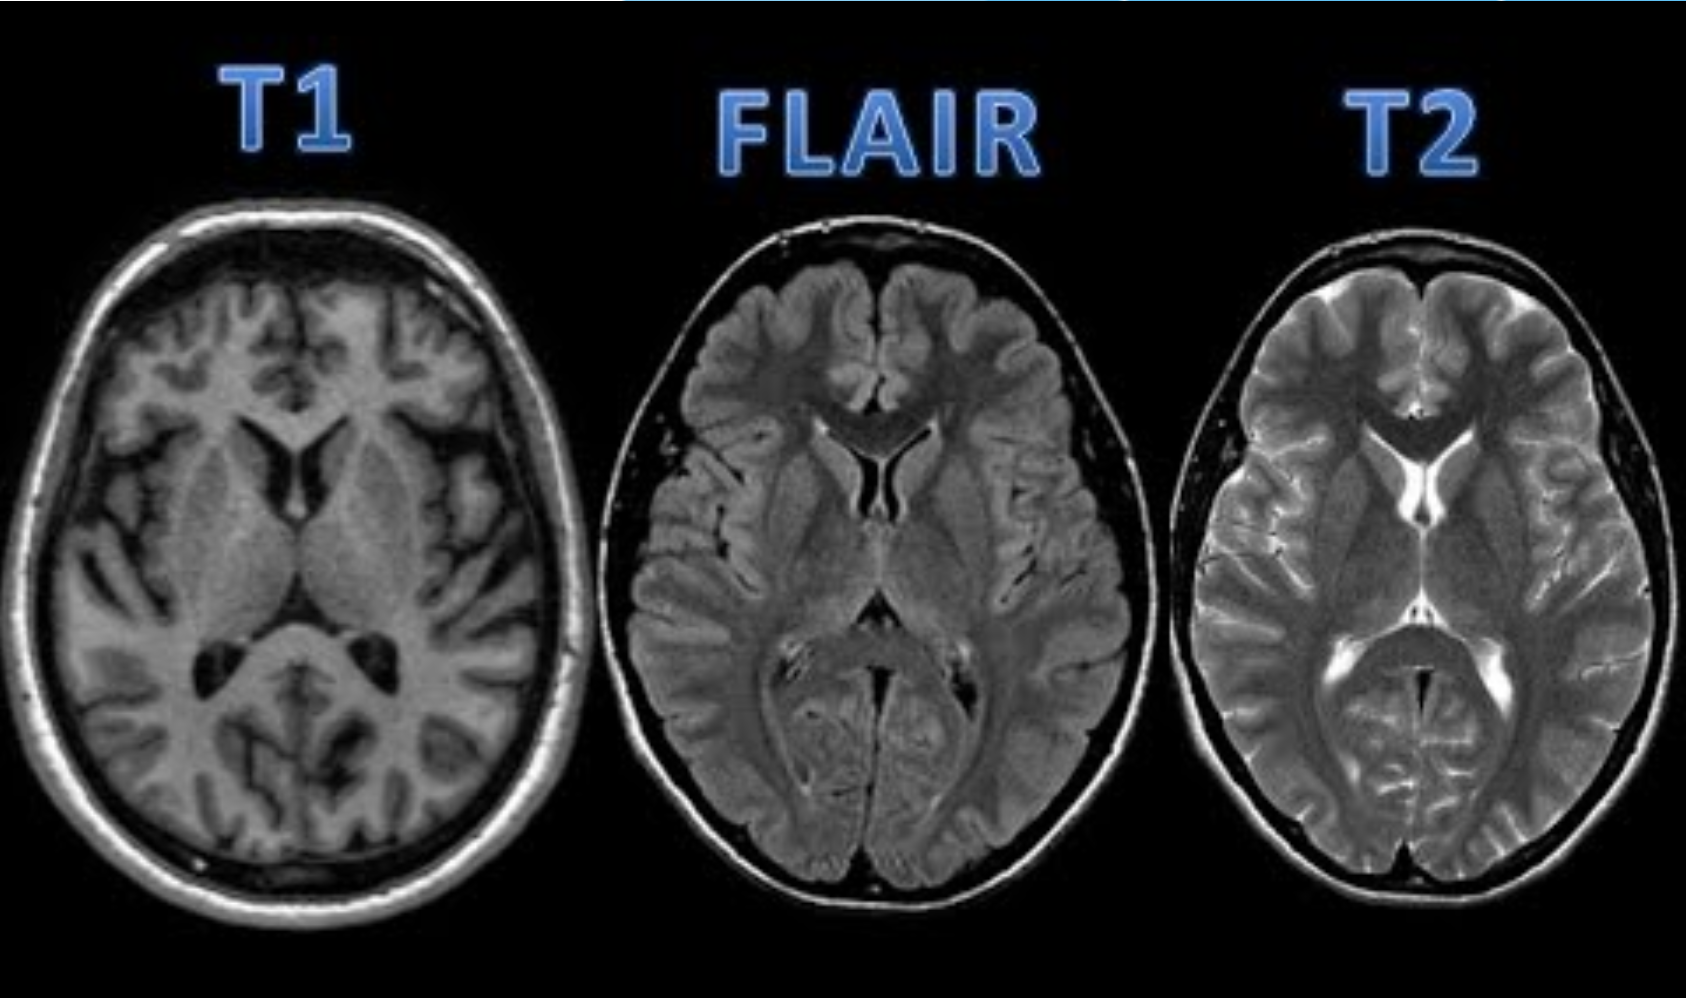

Exames de Imagem

incluir as imagens e as caracteristicas de em